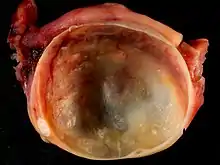

Histopathology

In case an ovarian cyst is surgically removed, a more definite diagnosis can be made by histopathology:

| Type | Subtype | Typical microscopy findings | Image |

| Dermoid cyst | Well-differentiated components from at least two germ layers (ectoderm, mesoderm and/or endoderm).[22] | ![]() | |